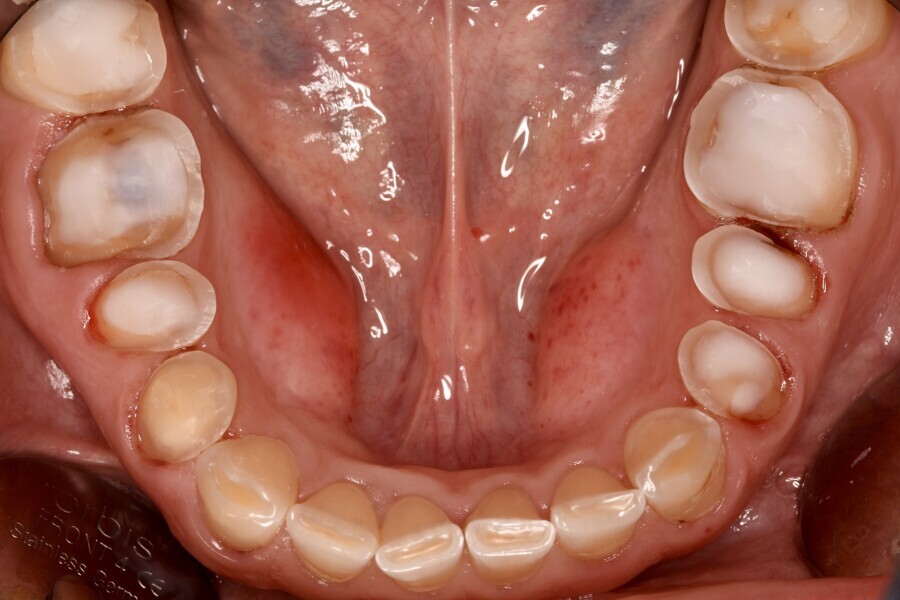

Fig. 1e: Almost complete loss of the occlusal relief in the lower jaw.